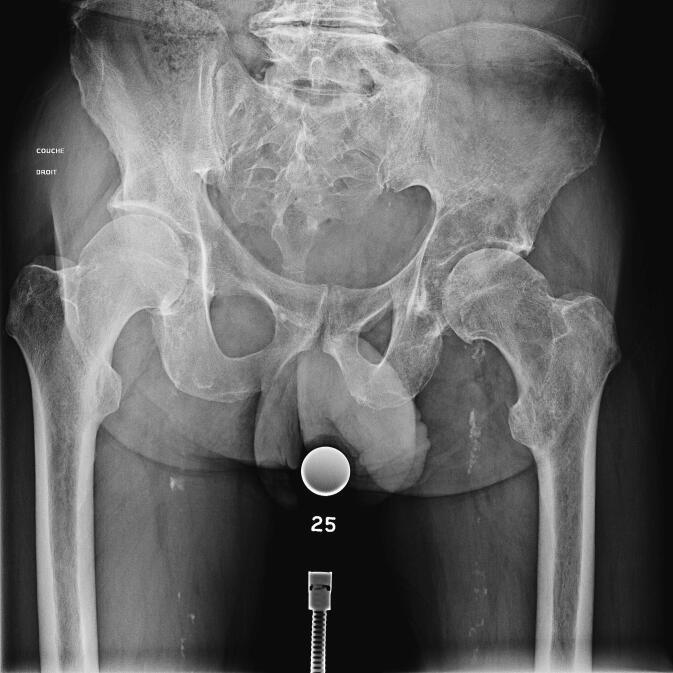

不进行刮除术的手术治疗对髋臼周围转移瘤是否有效?来自93例患者生存研究的见解。

Is surgery without curettage effective for periacetabular Metastasis? Insights from a survival study of 93 patients.

The main aim of this study was to analyse the 6-month survival rates in -acetabular metastasis patients undergoing total hip arthroplasty (THA) with an acetabular cage and without curettage. The secondary objectives were to analyse the global survival rates, the factors influencing patient survival and to evaluate mechanical complication rates after THA.

METHODS

This study was carried out on a cohort of 93 consecutive patients who underwent THA with an acetabular cage without curettage for acetabular metastasis or multiple myeloma lesions between 2010 and 2020. The National Death Registry was consulted to obtain the exact date of death of the patients; the minimum follow-up time was 2 years.

RESULTS

The 6-month survival rate for all types of cancer was 78 % [68 - 85], the 1-year survival rate was 66 % [55 - 74], and the 5-year survival rate was 26 % [17 - 36]. The median overall survival for the cohort was 24.37 months [16.10 - 32.63]. The mean overall survival was 46.02 months [32.89 - 59.16]. At last contact, 86 % of the operated patients were walking again.No patient died from surgery. The ECOG performance status score, the number of bone metastatic sites, the presence of visceral metastases and the number of lines of systemic therapy undertaken prior to surgery were negative survival factors. Three patients (3.2 %) had early prosthetic dislocation, 2 patients (2.2 %) showed aseptic loosening of her partial hip implant after 10 and 11 years respectively and 4 patients (4.3 %) had an early infection treated by debridement, antibiotics and implant retention to control the infection. During the follow-up period, no new femoral metastases were detected in any patient.

CONCLUSION

Surgery without curettage is an effective treatment for periacetabular metastasis. It gives reliable results, regardless of the type of acetabular lesion, allowing most patients to walk again and does not modify the patient's survival.